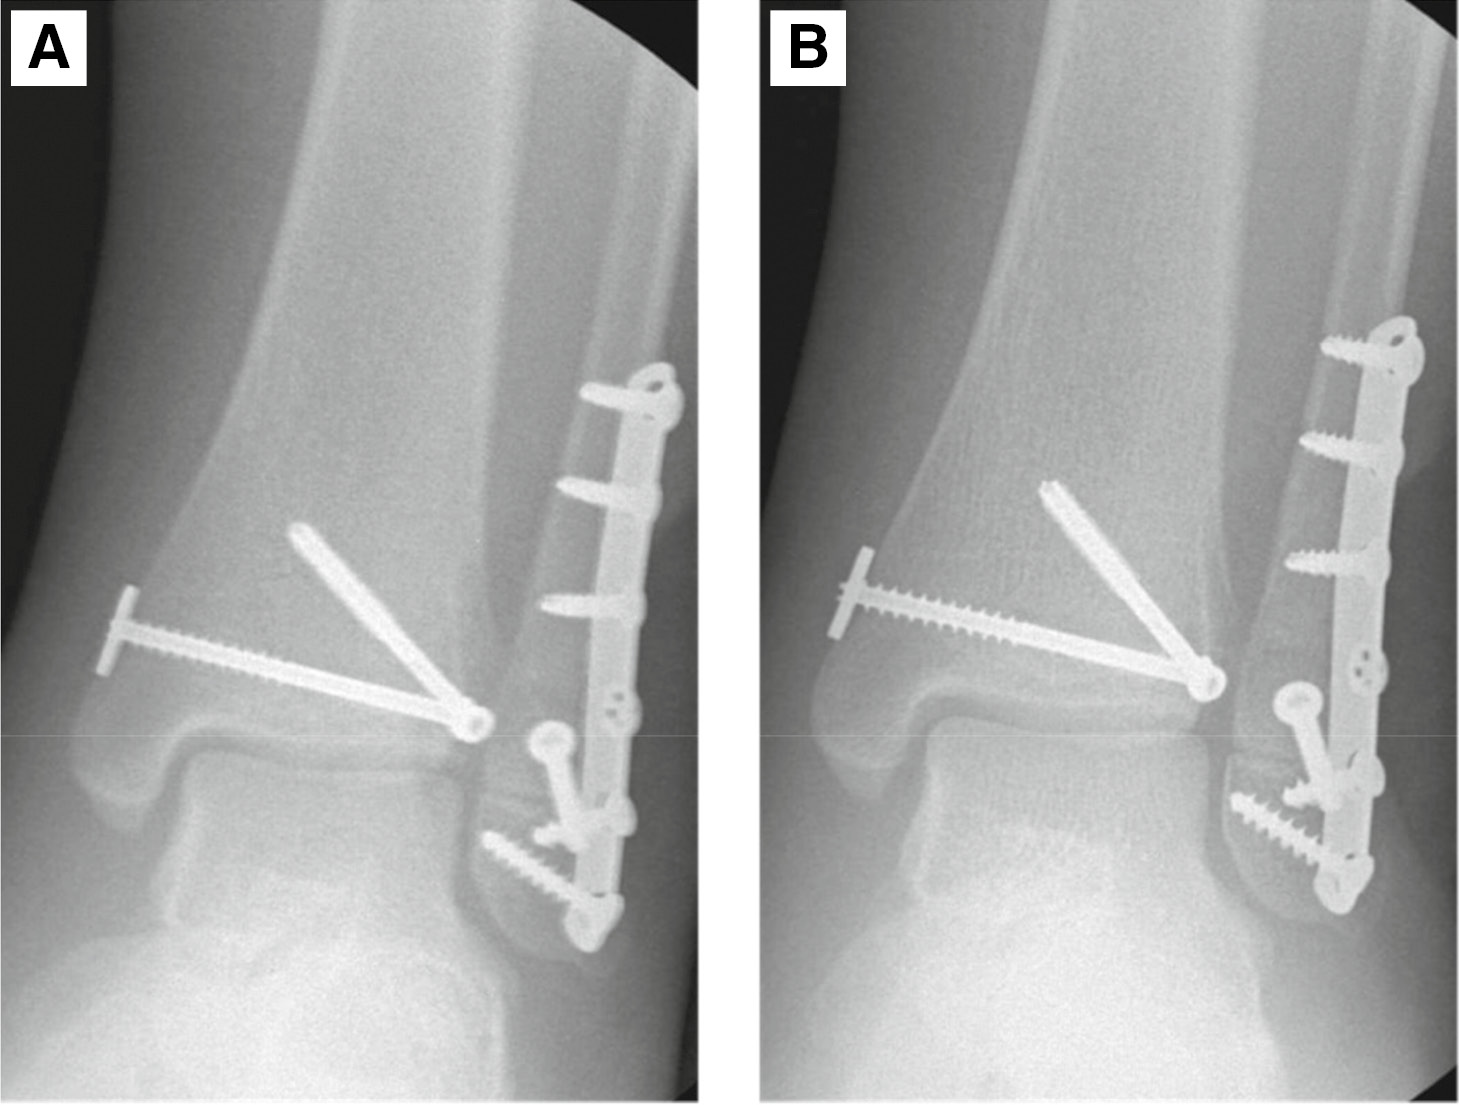

Because of this, we proceeded with fixation of the Salter-Harris II distal fibula fracture. However, repeat external rotation stress test after fibular fixation continued to show widening of the medial clear space and therefore, repair of the ankle syndesmosis was performed with suture button fixation (TightRope; Arthrex) in a similar fashion to the previous case. This reduced the talus, restored tibiofibular overlap, and repeat stress maneuvers demonstrated stabilization of the ankle (Figure 9). Postoperatively, he was placed in a short leg cast and made non-weight-bearing for a total of 6 weeks. At 6 weeks postoperation, he was transitioned to a CAM walker boot with gradual weight-bearing and ankle range of motion exercises. At 3 months, he was pain free with almost symmetric ankle range of motion. He was weaned out of the boot and continued working on strengthening with physical therapy. Radiographs showed anatomic alignment of the ankle with his fractures well healed (Figure 10). This example demonstrates that even in the setting of transitional type fractures, ankle stability should still be assessed and may need to be treated.

Figure 9. Intraoperative fluoroscopy after fibular and suture button fixation. (A) AP radiograph of the ankle. (B) Stress view of the ankle demonstrating no widening of the medial clear space and restored tibiofibular overlap compared to the AP radiograph.

jposna2022553_fig9.jpg

Figure 10. (A) Postoperative AP, (B) mortise, and (C) lateral radiographs of the ankle.

jposna2022553_fig10.jpg